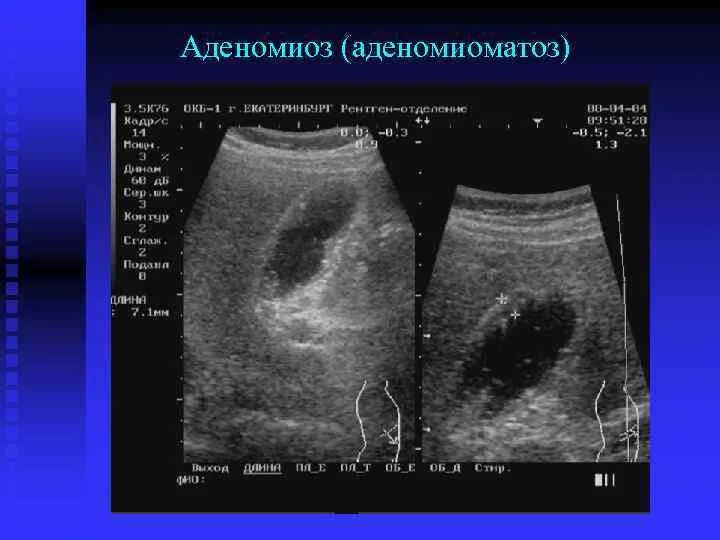

Диффузные изменения стенок желчного пузыря